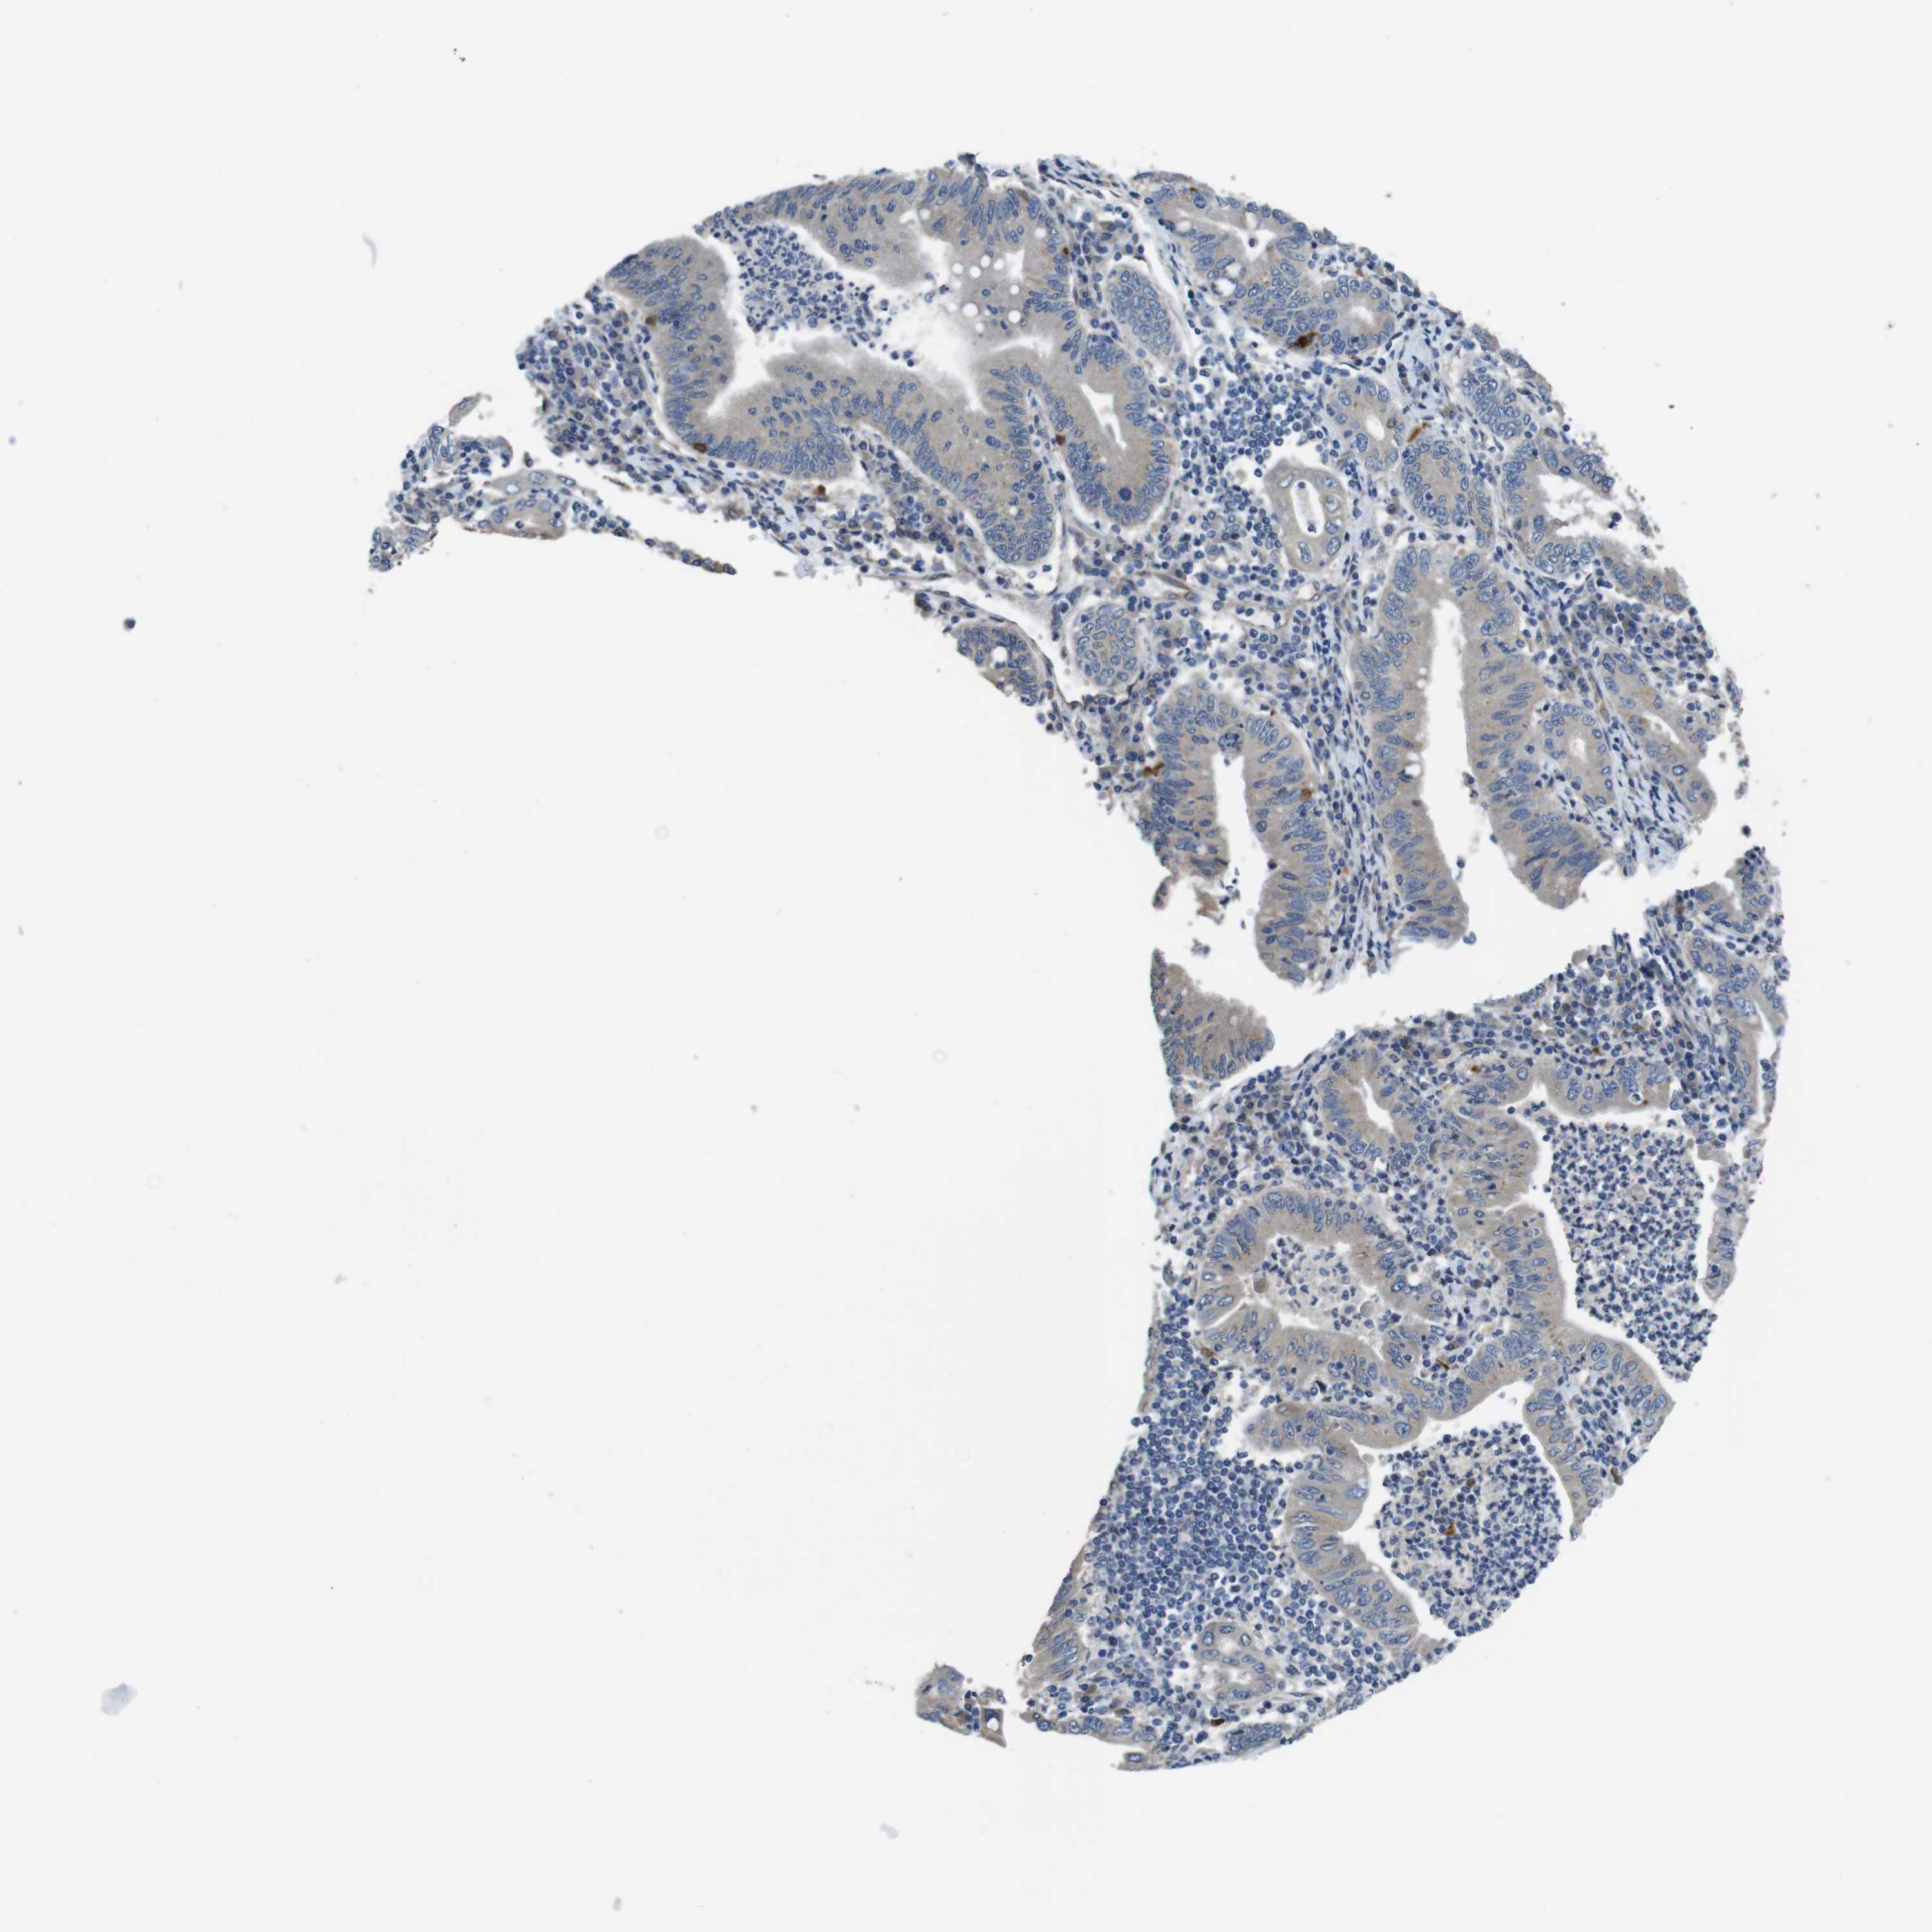

STOMACH CANCER - Protein expressioni

A mouse-over function shows sample information and annotation data. Click on an image to view it in a full screen mode. Samples can be filtered based on level of antibody staining by selecting one or several of the following categories: high, medium, low and not detected. The assay and annotation is described here.

Note that samples used for immunohistochemistry by the Human Protein Atlas do not correspond to samples in the TCGA dataset.

Antibody stainingi

Antibody staining in the annotated cell types in the current human tissue is reported as not detected, low, medium, or high, based on conventional immunohistochemistry profiling in selected tissues. This score is based on the combination of the staining intensity and fraction of stained cells.

Each image is clickable and will lead to virtual microscopy that enables deeper exploration of all samples and also displays staining intensity scores, fraction scores and subcellular localization as well as patient and tissue information for each sample.

Antibody HPA059131

Antibody CAB009936

Staining

High

Medium

Low

Not detected

Intensity

Strong

Moderate

Weak

Negative

Quantity

>75%

75%-25%

<25%

None

Location

Nuclear

Cytoplasmic/membranous

Cytoplasmic/membranous,nuclear

Adenocarcinoma, NOS

Adenocarcinoma, High grade